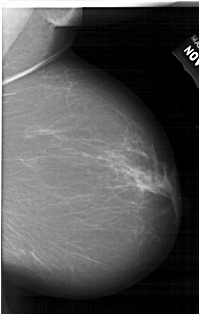

A_1519_1.RIGHT_MLO

RIGHT_MLO LINES 5956 PIXELS_PER_LINE 3781 BITS_PER_PIXEL 12 RESOLUTION 43.5 NON_OVERLAY